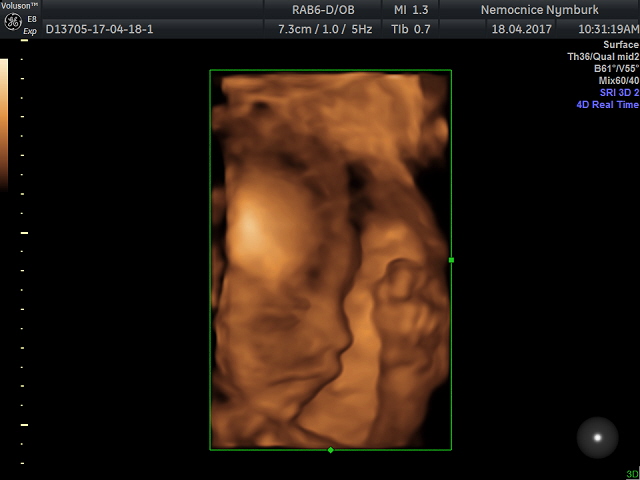

Ahoj všem, tak dnes mám po další kontrole 28+4 a vše odpovídá :-) maličká je v pořádku, je to pořád holka a dneska se i chtěla ukazovat :-) vyplazovala na nás dokonce i jazyk :-) má 1323g, zatím je položená zadečkem dole, ale prý je ještě spousty času aby se otočila. Doktor se divil, že na svou váhu mám super výsledky z cukrovky, že se to moc nestává, čípek zavřený, otoky nikde. Příští týden jdu ještě k obvoďákovi na ekg a pak ještě jednou zubař a kolečko mám snad kompletní - hurááá!

Slonice krásná fotka, koukám, že jsem se ani tím našim raráškem nepochlubilaLaughing monitor dechu jsem měla u dcerky a chci ho znovu, lépe se mi spí, teda já byla u dcery tak vyfluslá, že jsem spala i ve stoje u kočárkuLaughing zubaře jsem nějak podcenila, jdu zítra, hold budu mít jen jedno razítko a ještě se objednat k obvoďákovi. Teď řeším MD, protože mi končí doma určitá v červnu, tak to bude pro SSSZ oříšek vzhledem k dlouho neschopence, snad dostanu možnost vybrat si RD na 3 roky, uvidíme.